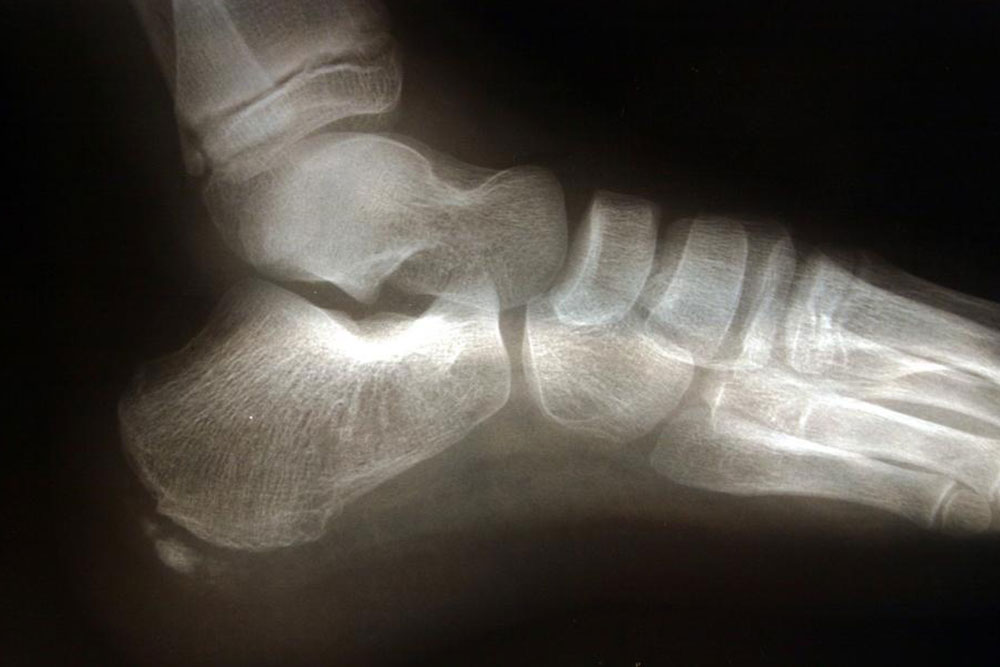

The pain that is experienced by an individual who suffers from osteoarthritis is inexplicable. The chronic condition is caused by friction in the joints of the bone. The ends of the bones are coated with a substance that is known as cartilage. However, when the cartilage breaks down, the ends of the bones are left bare and these lead to soreness and inflammation that increases with each passing day.